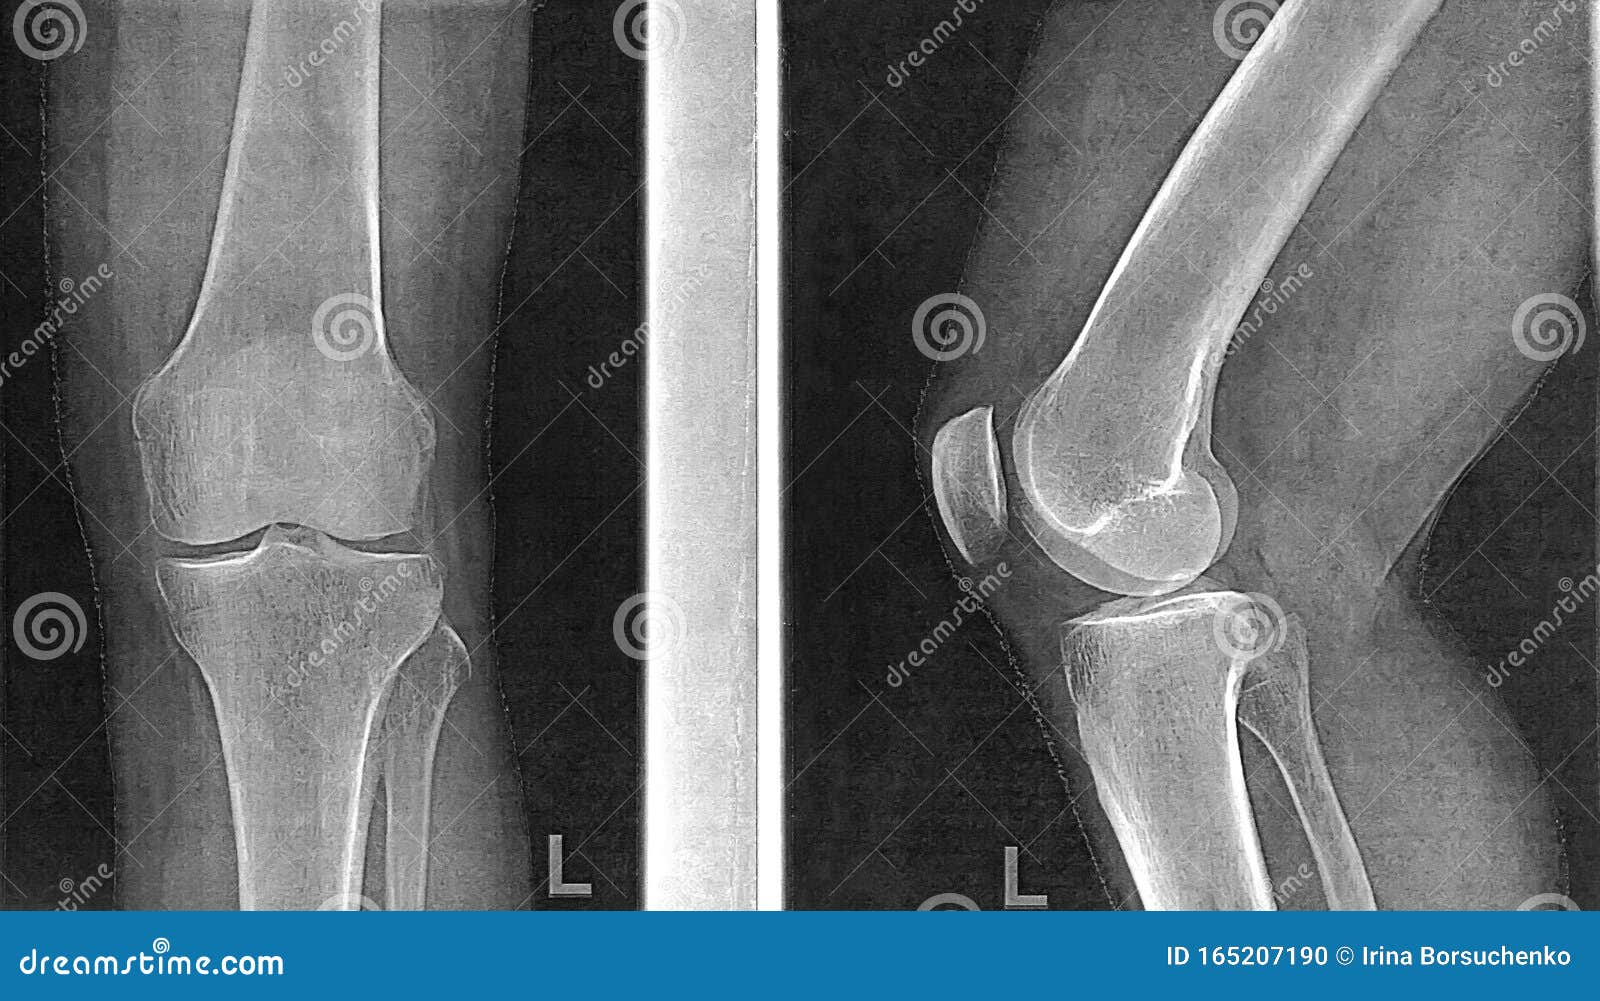

Рентгенограммы здорового коленного сустава: полезные советы и фотографии

На этой странице вы найдете подборку фотографий рентгенограмм здорового коленного сустава, а также полезные советы, которые помогут вам лучше понять, как выглядит нормальное состояние этого важного сустава.

Нормальная рентген-анатомия коленного сустава